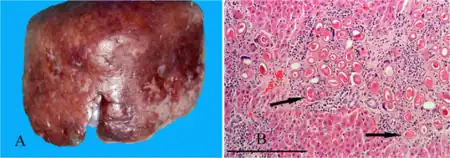

| a,b)Hepatic capillariasis | |

- Hepatic capillariasis, caused by Capillaria hepatica[4]